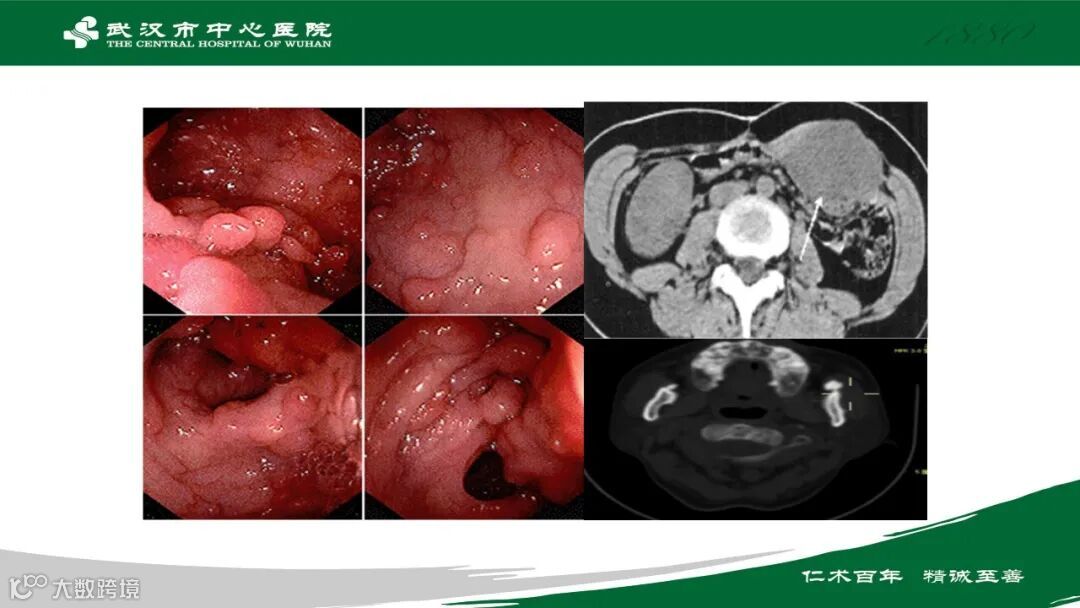

PET/CT检查已经成为临床工作必不可少的利器,在多种疾病的诊断中具有明显优势。如今越来越多县市级、区级医院安装设备,但是学习PET/CT检查及疾病诊断的资源却甚少。基于此,武汉市中心医院 周俊芬主任在鼎湖影像建立公益专栏,为大家分享自己的临床经验,欢迎大家持续关注。